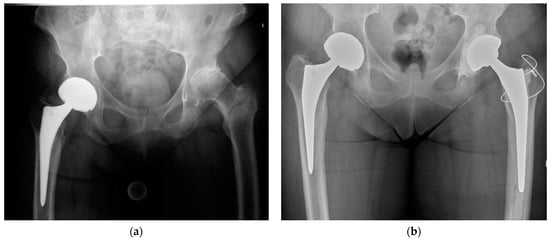

2. Indications

3.2. Implant Selection

3.3. Hip Abductor Mechanism Repair